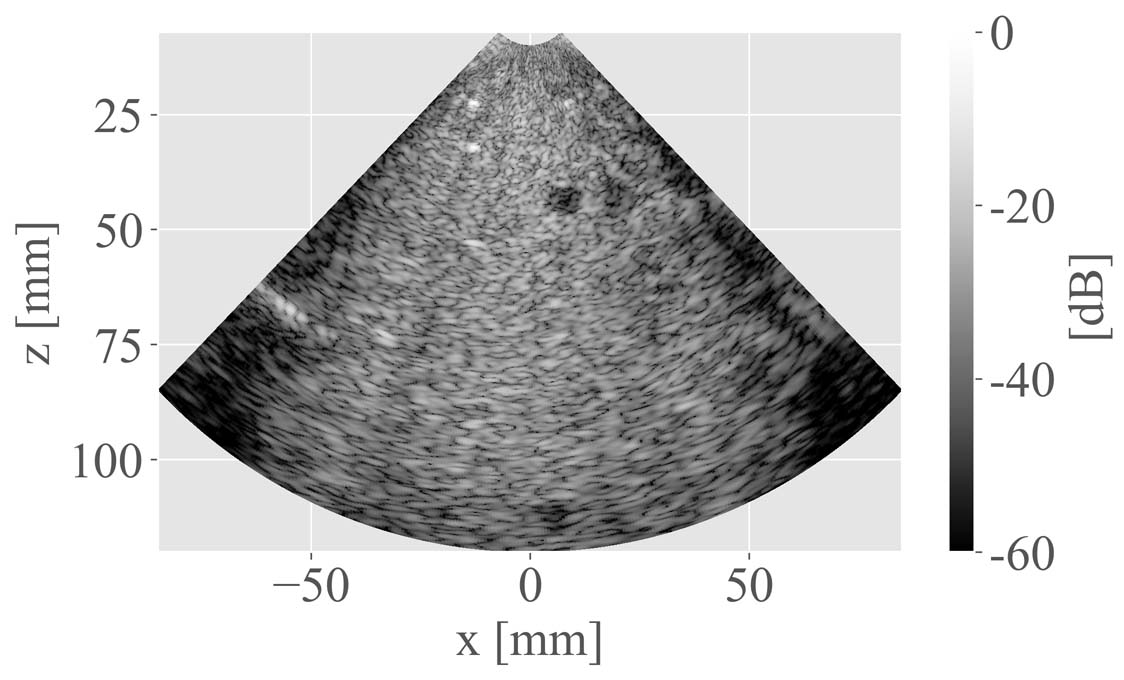

Figure 5: B-mode images obtained using IDNet and standard compounding. Top to bottom: in vivo tissues from the femoris muscle (a, b, c); in vitro tissues from the Gammex phantom (d, e, f); and in vitro tissues from the CIRS phantom (g, h, i). Left to right: compounding of 3 DWs; reconstruction of IDNet; and compounding of 31 DWs (reference).

The comparison of the visual quality between the reconstruction of IDNet and the coherent DW compounding method is shown in Fig. 5. It appears that the quality of the reconstruction of IDNet using only three DWs (Fig. 5b, 5e, and 5h) was improved compared to the images obtained from the standard compounding of the same three DWs (Fig. 5a, 5d, and 5g). In particular, the anatomical structures in Fig. 5b was enhanced compared to Fig. 5a. It can nevertheless be observed that the reconstruction of IDNet appeared to have an amplitude loss in the lateral region (Fig. 5e), as compared to the reference (Fig. 5f).

To quantitatively assess the improvement, we report in Table IV the PSNR, SSIM, and MI reached by IDNet and standard compounding of 3 DWs, using the compounding of 31 DWs as the reference. The reconstruction of IDNet showed a gain of 1.89 dB in PSNR, 0.1 in SSIM, and 0.31 in MI, as compared to the compounding of the same three DWs. In Fig. 6 and Fig. 7, we show the CR, CNR, and LR reached by IDNet and standard compounding. The CR and CNR were measured on the anechoic regions in the phantom (as shown in Fig. 5d, 5e and 5f). The LR was measured on the isolated scatterers (as shown in Fig. 5g, 5h and 5i). IDNet used a constant number of three DWs, whereas the results of standard compounding are given for an increasing number of DWs. From Fig. 6, it can be observed that IDNet reached a CR and CNR equivalent to those of the compounding of 21 DWs and 23 DWs, respectively, in both near and far fields. In Fig. 7, the LR evolution of standard compounding was consistent with the experimental observation from Zhang et al. [32]: LR value quickly dropped with two or three DWs and then reached a plateau with more DWs. IDNet reached an LR equivalent to that of the compounding of 3 DWs in the near and far fields, and the compounding of 21 DWs in the middle field.